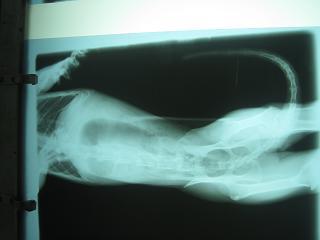

主題: 平溪張媽媽的2隻貓咪治療拉肚子 申請者姓名: 敏大哥 花色: 申請日期: 2012-07-01 21:56:37 申請者部落格: 申請者臉書網址: 所在縣市/合作醫院: 台北市/詠欣動物醫院 治療費用: 5200元 需求人數: 23人 已結案 (2012-12-01 21:24:18) 報名人員: Anita Yin(已付款)、Anita Yin(已付款)、Angel Kuo(已付款)、小可愛(已付款)、Hui-Yi Lo(已付款)、Mia Chang(已付款)、Milkbau Lu(已付款)、Sherry Fang(已付款)、Sherry Fang(已付款)、Juwan Liu(已付款)、冥王星獅子(已付款)、curry0(已付款)、Nina Chong(已付款)、Nicoletta Fon Fon(已付款)、Layla Hsu(已付款)、范立縈(已付款)、鳳姐(已付款)、Civie Szu Wei Shen(已付款)、Jakei Chia(已付款)、Jakei Chia(已付款)、Jakei Chia(已付款)、Shih Ju Chiu(已付款)、沙粒小貓(已付款)、 候補人員: 小舟、小舟、 動物病情說明: 貓咪這幾天吃不太下,其中鼻子白的金吉拉有血便,檢查出有梨型鞭毛蟲.治療幾天後,血便的金吉拉食慾仍不好.再幫他驗血 照x光.確認無其他問題.大腸有明顯發炎.則繼續吃藥 飲食控制.